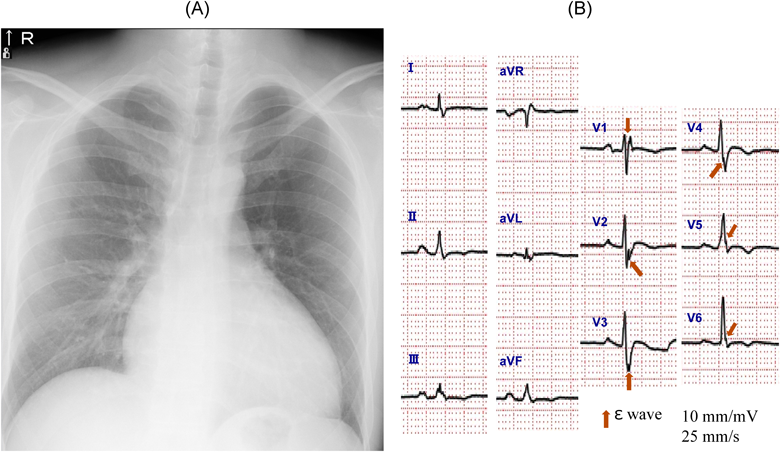

ダビガトランで右室内血栓が消失した不整脈原性右室心筋症の1例Dissolution of a Right Ventricular Thrombus with Dabigatran Etexilate in Arrhythmogenic Right Ventricular Cardiomyopathy